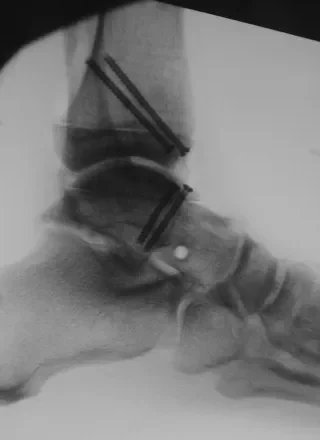

Tibiotalar Allograft Reconstruction Surgery

Tibiotalar allograft reconstruction is a joint-preserving surgical procedure used to treat focal or extensive cartilage and bone loss of the ankle joint, most commonly involving the talar dome or tibial plafond. The procedure aims to restore joint surface anatomy using donor (allograft) bone and cartilage, allowing pain relief while preserving ankle motion.

Tibiotalar allograft reconstruction involves removing damaged cartilage and bone from the ankle joint and replacing it with a size-matched osteochondral allograft. The graft is carefully shaped to restore the contour of the joint surface and secured in place to allow incorporation and healing.